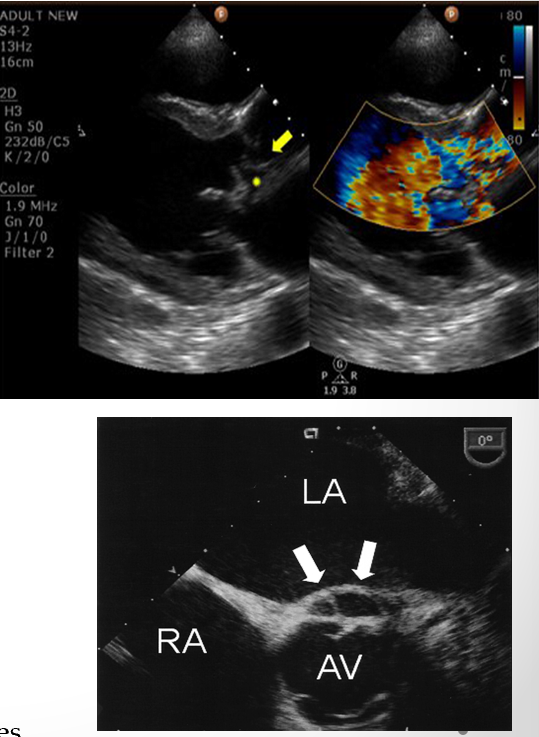

color flow doppler is used to assess what in IE vegetations?

hemodynamic effect

what is seen here?

tricuspid valve vegetation w/ severe regurg